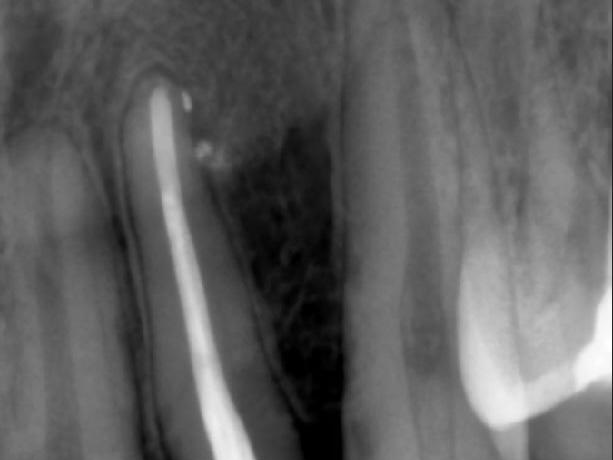

Примеры работ

• Лечение кариеса.

• Замена старой пломбы и лечение кариеса.